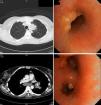

Una mujer de 45años residente en India hasta hacía 8meses consultó por un cuadro de 3meses de evolución de fiebre diaria hasta 38°C, anorexia, pérdida de peso, tos seca y disnea, sin mejoría tras 7días de tratamiento con amoxicilina-clavulánico. A la exploración tenía buen estado general; solo destacaban 2nódulos subcutáneos de 1cm en el hipocondrio izquierdo, móviles, de consistencia gomosa, algo dolorosos y sin signos inflamatorios, con otro similar en la mano izquierda. En la analítica se detectó anemia, leucocitosis y trombocitosis. La radiografía de tórax mostró una masa en el mediastino anterior, que en la tomografía axial computarizada (TAC) se informó como «masa en lóbulo superior izquierdo y región hiliar ipsilateral, con infiltración de mediastino anterior, que estenosa la luz bronquial; adenopatías subcarinales y paratraqueales ipsilaterales, junto con múltiples nódulos independientes en pulmón izquierdo, implantes pleurales y nódulos subcutáneos abdominales». En la broncoscopia la mucosa estaba inflamada, con implantes de aspecto tumoral y estenosis bronquial izquierda. En las biopsias se descartó malignidad, pero tanto en las bronquiales como en la de uno de los nódulos abdominales se observaron granulomas no necrosantes. Con cultivos inicialmente negativos, creció después un Mycobacterium tuberculosis multisensible en esputo, por lo que se diagnosticó de TBC diseminada con afectación endobronquial de tipo tumoral y cutánea. La paciente mejoró rápidamente con tuberculostáticos y corticoides. La broncoscopia fue normal a los 6meses, mientras que la TAC solo mostraba engrosamiento residual de partes blandas (fig. 1).

La TBC endobronquial aparece en el 5-40% de las TBC pulmonares activas, aunque está infradiagnosticada2,3. Se origina por implante directo desde una cavidad, foco tuberculoso o ganglio mediastínico adyacente, o por diseminación linfática o hematógena3,4. Sus síntomas son: tos (71-100%), fiebre (50%), pérdida de peso (30%), hemoptisis (18-25%), disnea, dolor torácico y anorexia2,4,5. Tanto la duración de los síntomas como la evolución de la enfermedad son variables, desde la resolución completa hasta la aparición de bronquiectasias, obstrucciones bronquiales o atelectasias. La prueba microbiológica más rentable es el lavado bronquioalveolar, por encima del esputo2–5. La radiografía puede mostrar infiltrados alveolares (35-43%), nódulos (25%), lesiones cavitadas (12%), derrame pleural (9%) o engrosamiento hiliar (7%), aunque puede ser normal en un 10-20%2,3. La TAC es útil para valorar la extensión, el grado de obstrucción bronquial y la evolución, y puede sustituir a la broncoscopia en el seguimiento4, aunque esta es de elección en el diagnóstico.